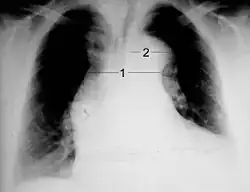

Chest X-ray

Chest radiography may although demonstrate a change in the morphology of the thoracic aorta which can be seen in aortic dissection. Classically, new widening of the mediastinum on radiograph is of moderate sensitivity for detecting an ascending aortic dissection; however, this finding is of low specificity, as many other conditions can cause apparent widening of the mediastinum.

There are several other associated radiographic findings:

- The "calcium sign" describes an apparent separation of the intimal calcification from the outer aortic margin by greater than 10 mm.

- Pleural effusions, more commonly in descending aortic dissections, and typically left-sided.

- Other: the obliteration of the aortic knob, depression of the left mainstem bronchus, loss of the paratracheal stripe, and tracheal deviation.

Importantly, about 12 to 20% of aortic dissections are not detectable by chest radiograph; therefore, a "normal" chest radiograph does not rule out aortic dissection. If there is high clinical suspicion, a more sensitive imaging test (CT angiogram, MR angiography, or transesophageal echo) may be warranted.